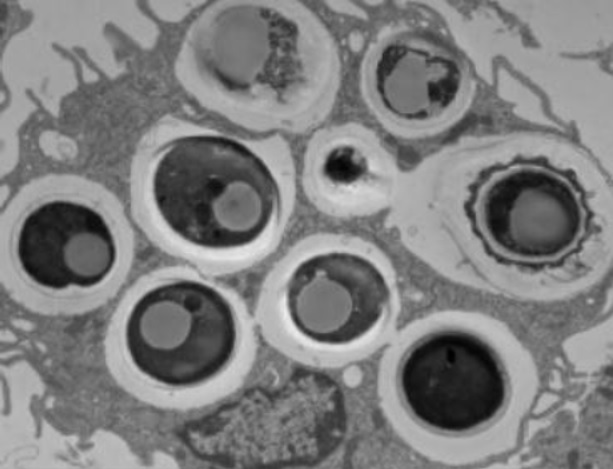

Quels mécanismes ? L’étude de souris modèles de cicatrisation intestinale altérée représentatives des lésions intestinales observées chez les patients atteints de la maladie de Crohn, constate que les niveaux de D. hansenii sont également significativement plus élevés dans les plaies non cicatrisées. La levure se développait dans ces plaies plutôt à proximité des macrophages.